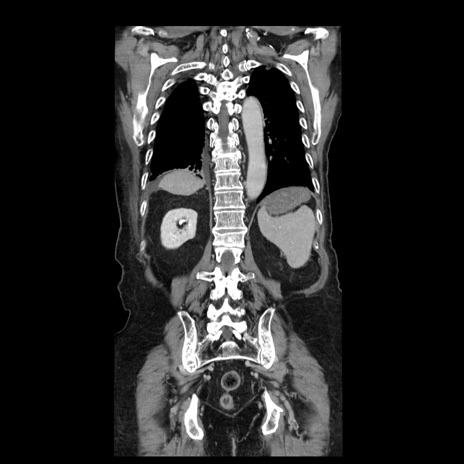

症例21(冠状断像)

【症例】70歳代男性

【主訴】腹痛

【現病歴】肝硬変・肝細胞癌にてかかりつけの方。約9時間前に食後より腹痛出現。症状が徐々に増悪し、嘔吐出現したため来院。

【既往歴】肝硬変、肝細胞癌(RFA、TACE後)

【身体所見】意識清明、表情苦悶様、BT 36℃、BP 129/78mmHg、P 88bpm、SpO2 97%(RA)、右上腹部から心窩部にかけて圧痛あり、反跳痛なし、筋性防御あり。

【データ】WBC 5800、CRP 0.16